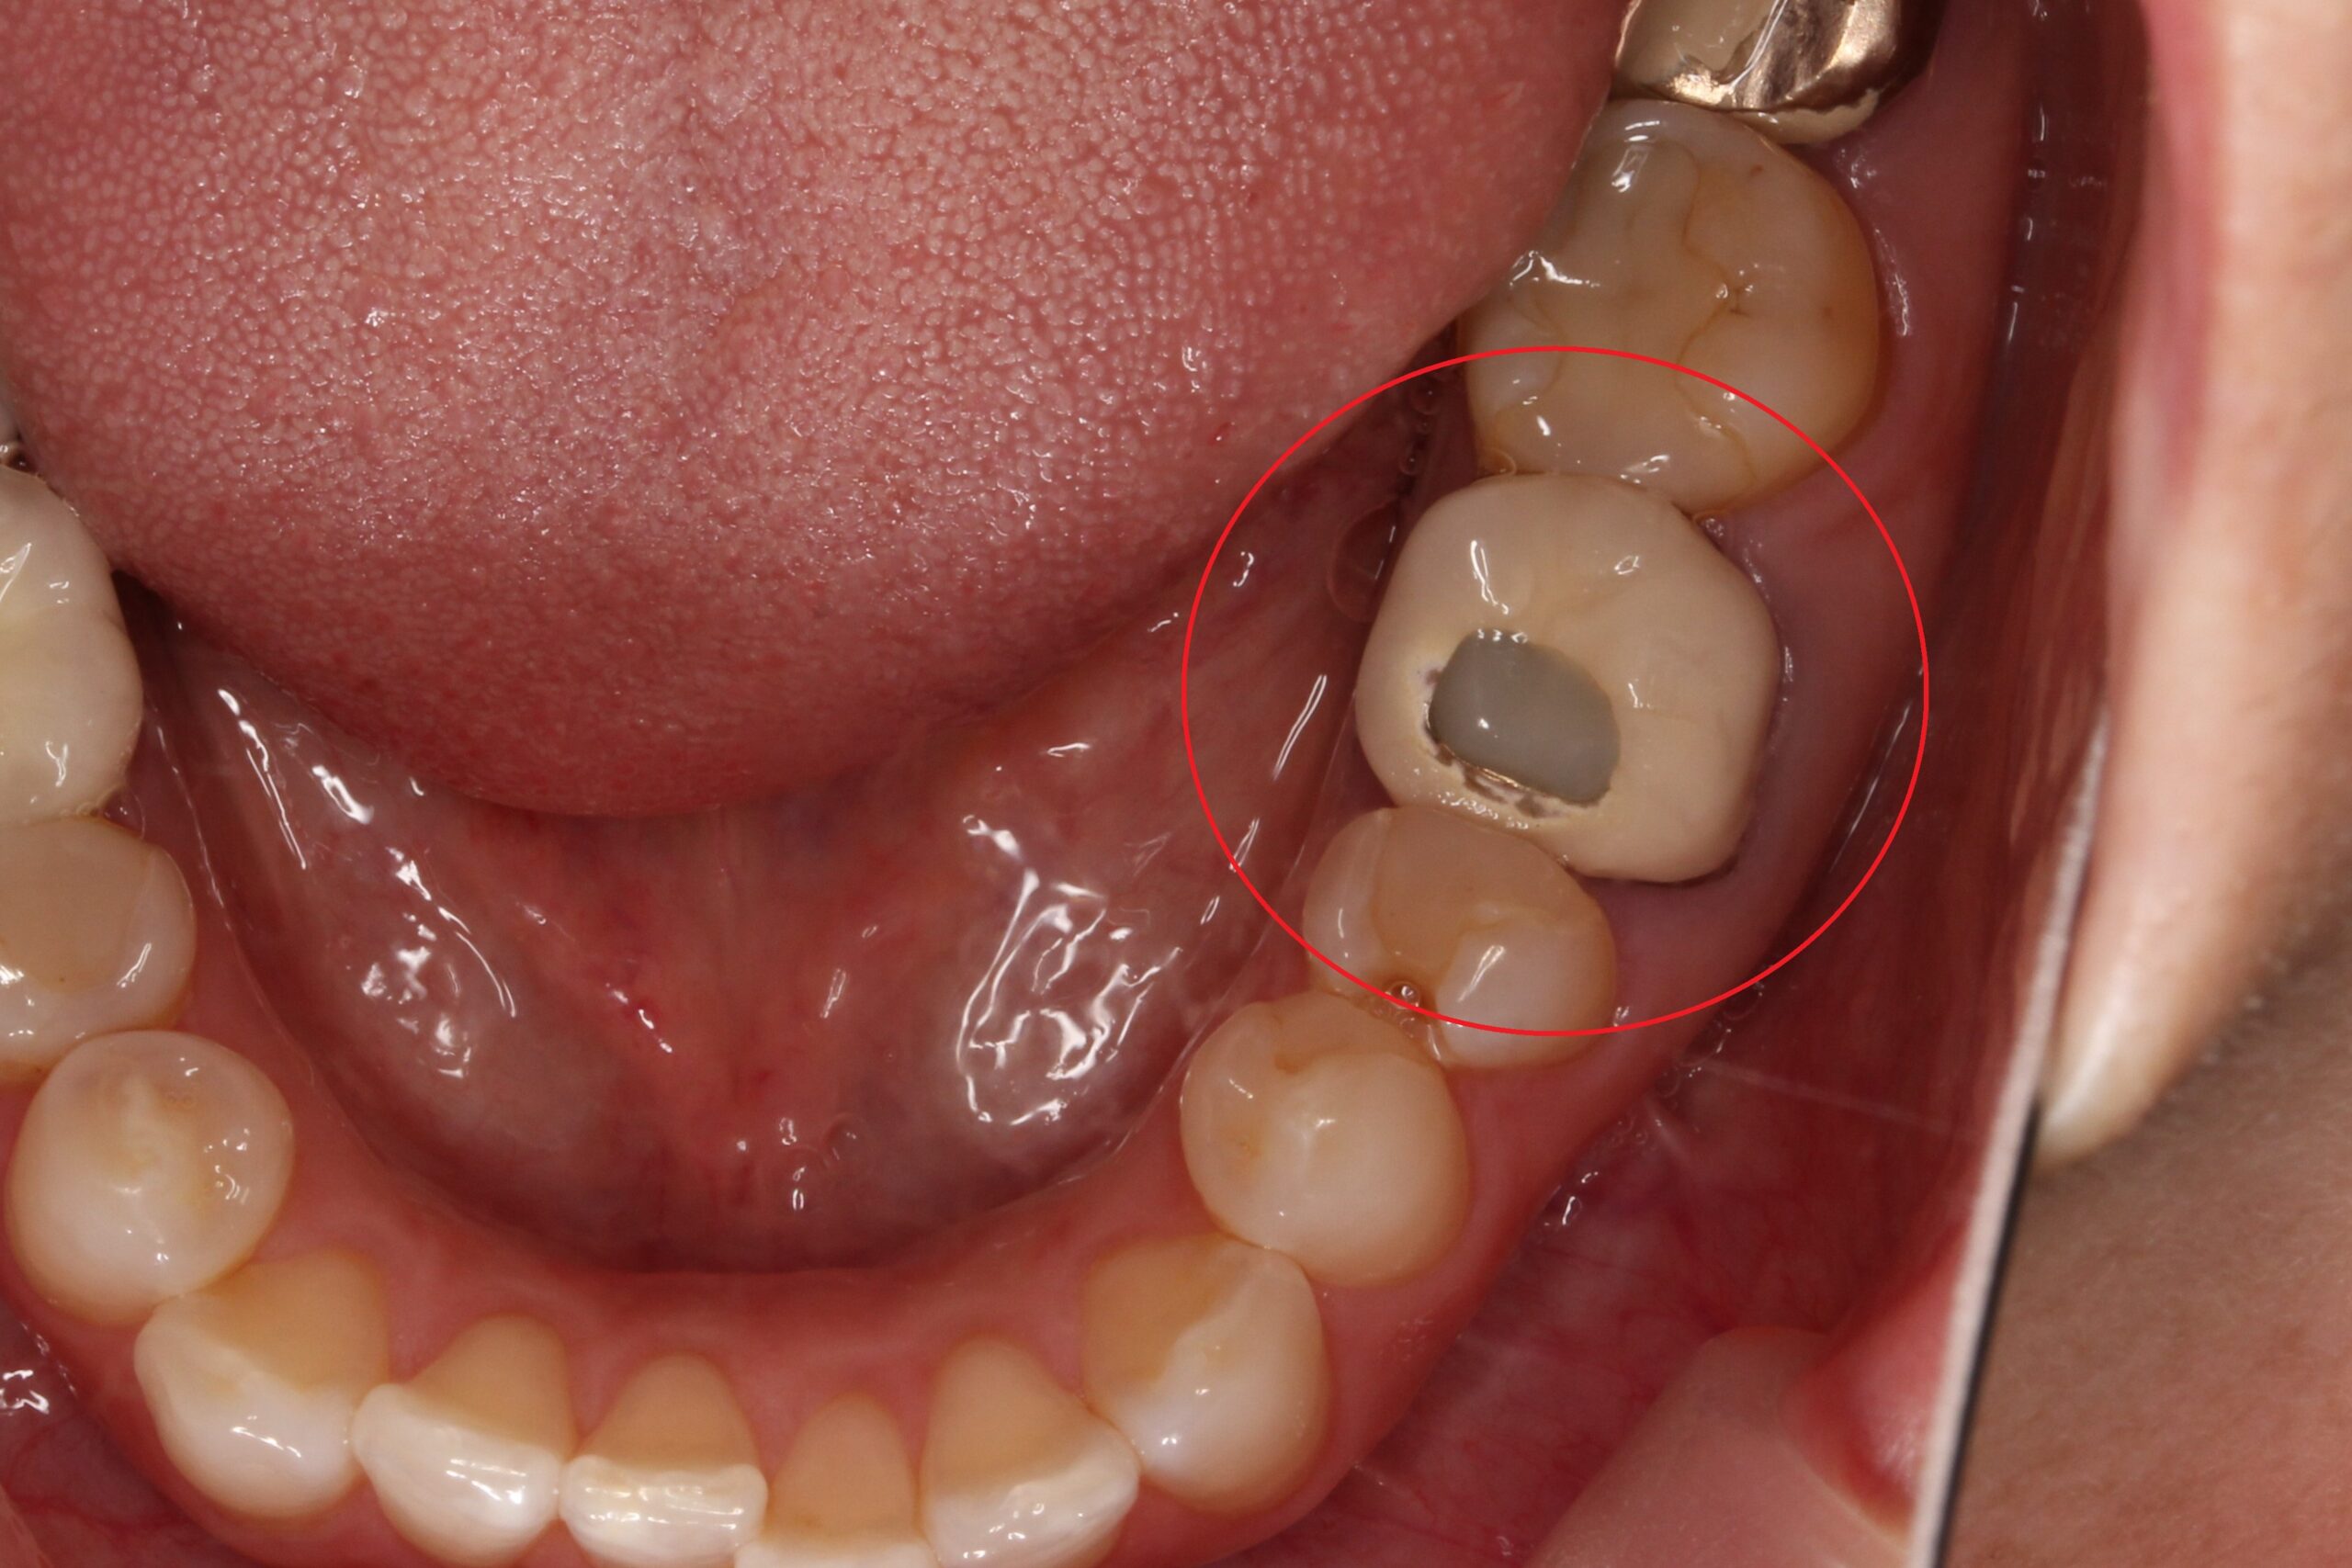

• Before

After

30代女性 歯に違和感。神経死んでる。根管治療。